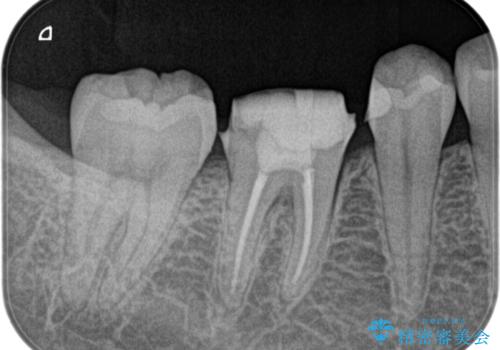

- 定期検診にて膿の出口を見つけたことを主訴に来院されました。

検査の結果、診断を歯髄壊死、症候性根尖性歯周炎とし抜髄を行っております。

根管充填はCWCTにて行なっています。